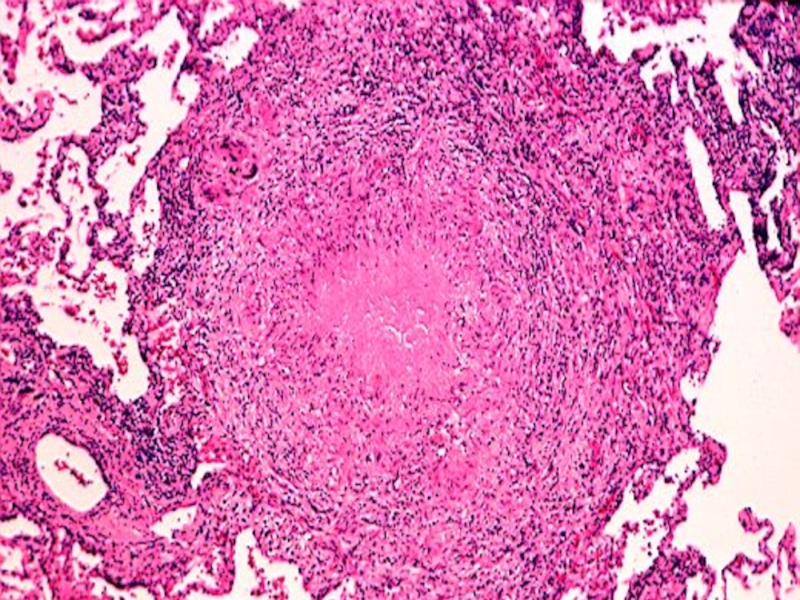

Слайд 110Cavity wall (LM) : three layers

1.inner:caseous necrosis

2.midial:tuberculous granulation tissue

3.outer: fibrous

tissue

1

2

3

Cavity wall (LM) : three layers1.inner:caseous necrosis2.midial:tuberculous granulation tissue3.outer: fibrous tissue123